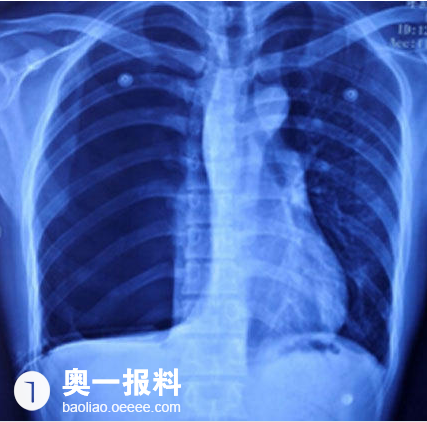

深圳小伙右肺突然不见 左肺差点也没了_报料_